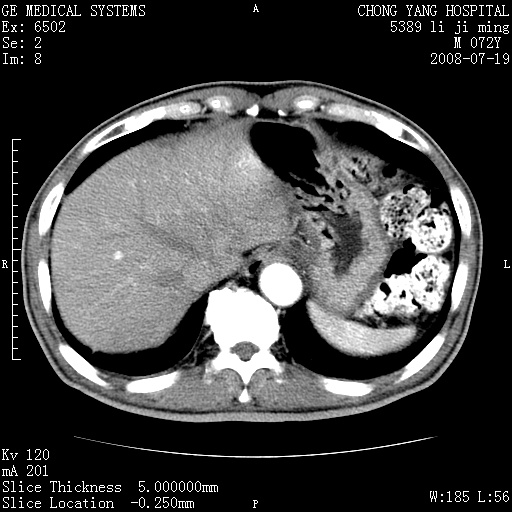

以下是引用zjzjr在2008-7-19 20:57:00的发言:[br]胰头增大,边缘模糊,周围可见渗出影,右侧肾前筋膜增厚.支持胰腺炎.

以下是引用不学无术在2008-7-19 23:15:00的发言:[br]胰腺增大尤以胰头明显,边缘模糊,周围可见渗出影,右侧肾前筋膜增厚,肠管於涨.支持胰腺炎